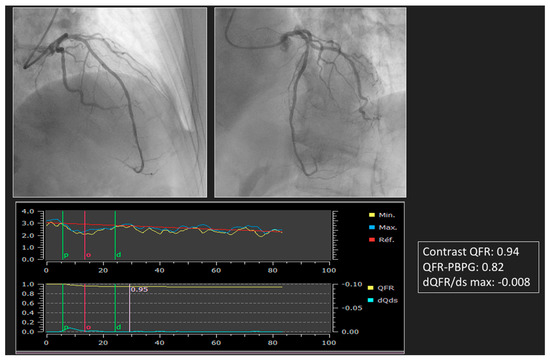

| Dai et al. [30], 2022 | 1335 | QFR-PBPG, dQFR/ds | Prognosis of 4 patient groups defined by predominant focal disease (QFR-PBPG > 0.78) with (dQFR/dt ≥ 0.005/mm) and without major gradient and predominant diffuse disease (QFR-PBPG ≤ 0.78) with and without major gradient by VOCO in a 2-year retrospective study | At 2 years, VOCO was lowest in patients with predominant focal without major gradient (1.4% vs. 5.4% in predominant focal with major gradient patients vs. 4.8% in predominant diffuse without major gradient patients vs. 8.5% in predominant diffuse with major gradient patients, all p < 0.05), whereas there was no prognostic value for classifications by visual assessment. Physiological residual disease patterns were independently associated with VOCO and showed increased prognostic value when introduced to a model with clinical risk factors only (C index: 0.77 vs. 0.68, p < 0.008; NRI: 0.65, p < 0.001; IDI: 0.020, p < 0.001). |